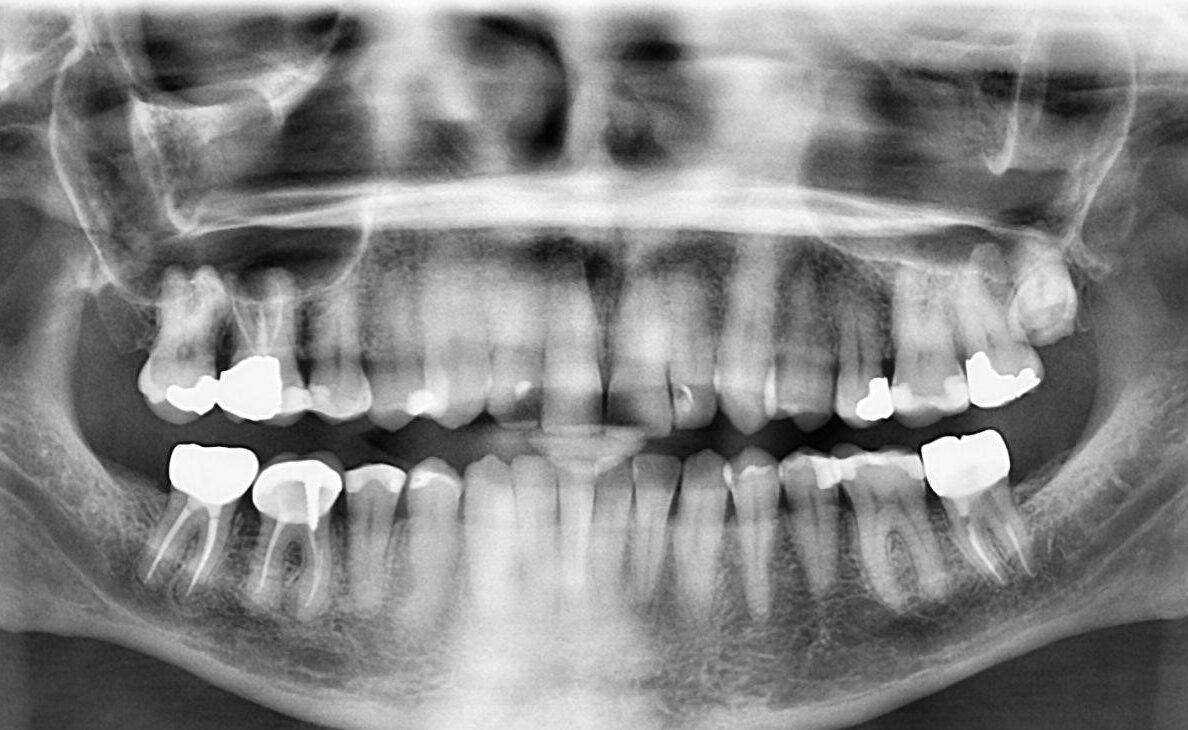

1.  What option cannot be selected for this panoramic X ray?

2. What option cannot be selected for upper jaw of this panoramic X ray?

3. What option cannot be selected for lower jaw of this panoramic X ray?